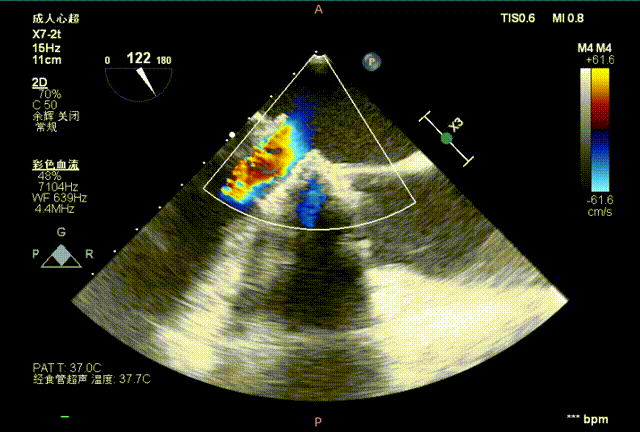

二尖瓣

术前

术前术后流速压差对比,术前最大速度265cm/s,平均速度189cm/s,最大压力梯度28mmHg,平均压力梯度16mmHg;术后最大速度194cm/s,平均速度137cm/s,最大压力梯度15mmHg,平均压力梯度8mmHg: